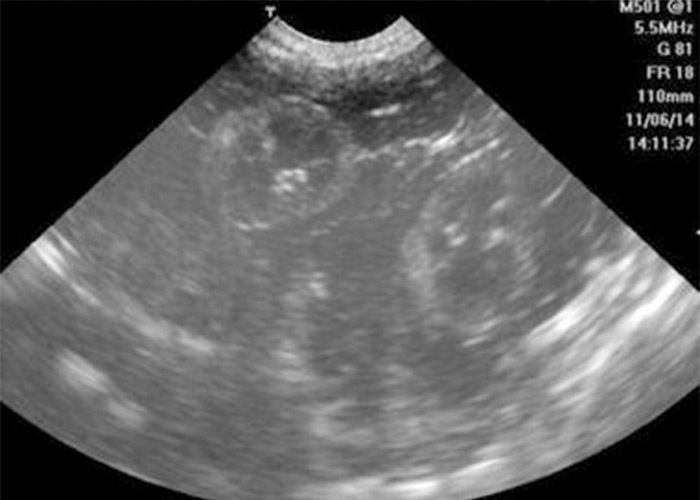

大约在受精的第7天,受精卵会分化出滋养层,滋养层的细胞就开始分泌绒毛膜促性腺激素,简称HCG。正常怀孕,在停经28天左右,在血液就可以检测到HCG,而且通过B超可以发现孕囊。

(图片来源于网络)

但生化妊娠,血液中虽然可以检测到HCG升高,大于25mIU/mL,或者早孕试纸的检测成阳性。可是,超声检查中是看不到孕囊的,原因是受精卵着床失败。